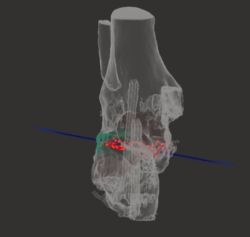

Figura 2. Modelo 3D del defecto del astrágalo.

- Obtención de la forma real del defecto combinando el astrágalo con una imagen especular del astrágalo contralateral (Figura 2).